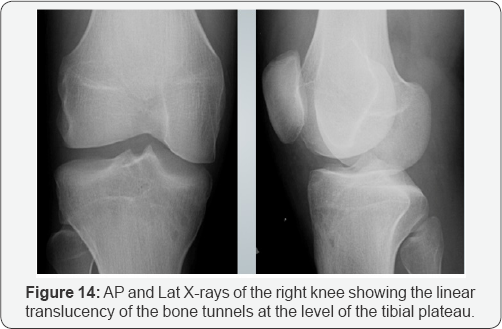

iii. Expected postoperative changes (Figure 14) and micrometallic artifacts due to surgery (Figure 15).